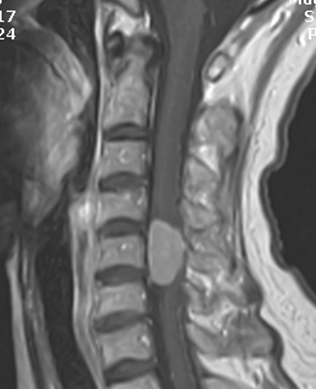

<흉추의

척추체와 후궁의 섬유주와 겉질뼈의 파괴가 관찰됨. 혈관종.>

척추경의 미란, 척추체의 파괴와 압박 골절 등을 볼 수 있습니다.

척추의 무기질침착과 겉질뼈의 상태를 정확히 파악하여 척추의 파괴 정도를 평가할 수 있습니다.

척추의 무기질침착과 겉질뼈의 상태를 정확히 파악하여 척추의 파괴 정도를 평가할 수 있습니다.